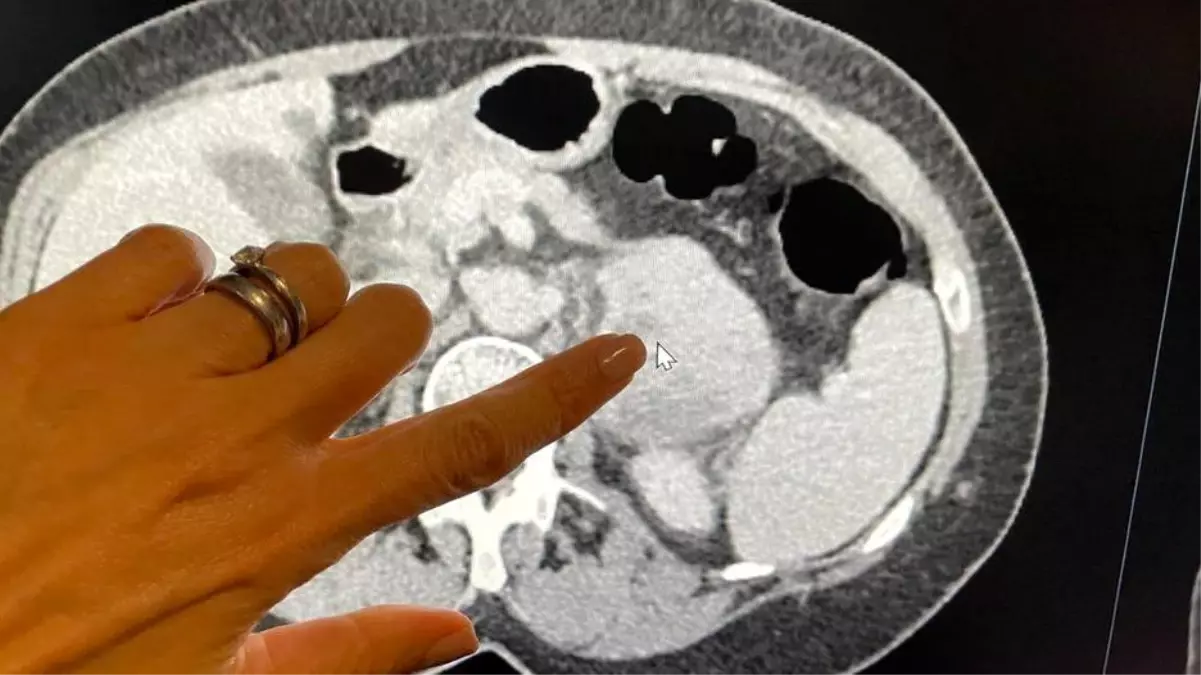

Tıp dergisi Lancet Onkoloji’de yayımlanan araştırmada, adlı, karın bölgesinin arkasında gelişen ve nadir görülen bir kanser türü olan retroperitoneal sarkom bulunan 170 hastanın görüntülemelerinde, gözle görülemeyen işaretleri bulmak için radyomiks adlı bir teknik kullanıldı.

Yapay zeka algoritması, bu görüntülemelerden elde edilen verilerle ABD ve Avrupa’daki diğer 89 hastanın görüntülemelerinde hastalığın saldırganlık derecesini, kanserli dokunun bir mikroskop altında incelendiği biyopsi işleminden çok daha doğru bir şekilde tespit etti.

Diş hemşiresi Tina McLaughlan’a geçen yıl Haziran’da karın bölgesinin arkasındaki sarkom nedeniyle çektiği karın ağrılarının ardından, doktorlar sorunu tespit edebilmek için bilgisayarlı tomografi (CT) yöntemini kullandı.